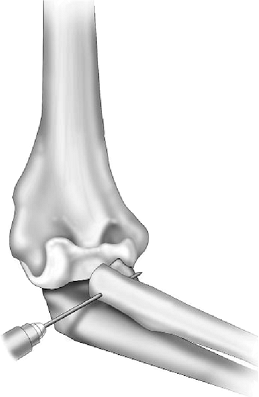

The goal of the procedure is to interpose the anconeus

between the proximal radius and between the capitellum and ulna. The

lateral collateral ligament is managed as described earlier. The

interval between the proximal radius and the ulna is developed. If

capitellar fixation is desired, two drill holes are placed in the

capitellum approximately 5 to 7 mm apart, as earlier. A drill hole is

then placed across both cortices of the resected proximal radius from

lateral to medial with the forearm in neutral rotation (Fig. 23-12).

Figure 23-12. A through-and-through drill hole is placed in the proximal radius.

|